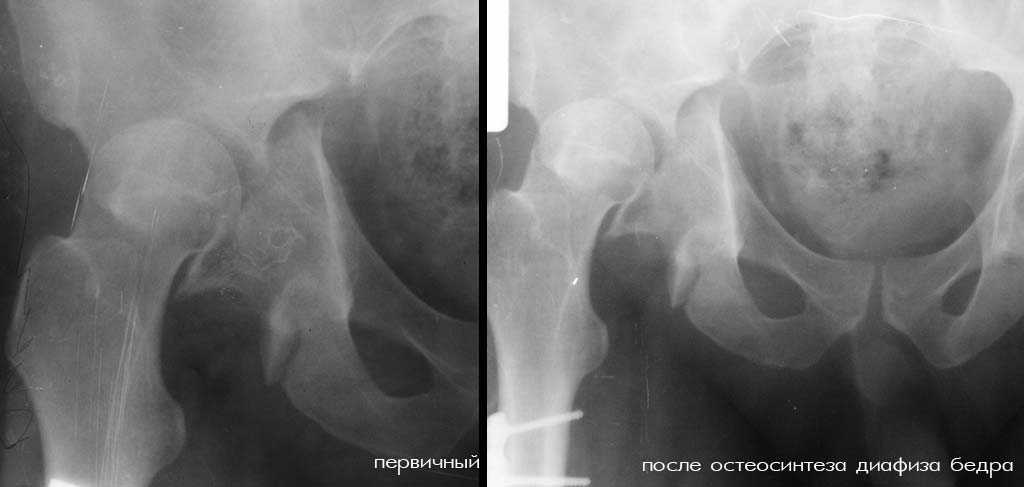

К нам переведен больной 36 лет (175 см рост, 105 кг масса тела), который 64 дня назад в ДТП получил множественную скелетную травму: перелом вертлужной впадины справа с задним вывихом бедра и повреждением крестцово-подвздошного сочленения справа, оскольчатым (тип C3) переломом диафиза правого бедра на границе с/3 - н/3, открытый (тип III В по Каплану-Марковой) краевой перелом мыщелков правой большеберцовой кости, закрытый поперечный перелом диафизов костей правой голени на границе с/3-н/3 (т.е. все повреждения справа). Судя по анамнезу, имело место сдавление правой голени и бедра около 1,5 часов. В ЦРБ (по месту получения травмы) был доставлен в тяжёлом травматическом шоке, отмечались признаки ОПН (в частности, олигурия и подъём уровня креатинина выше 300 ммоль/л). Судя по анамнезу, более месяца сохранялся резко выраженный отёк правого бедра. Из выписки известно, что безуспешные попытки закрытой репозиции вывиха бедра были выполнены при поступлении в ЦРБ. Больному также выполнен накостный остеосинтез диафиза правого бедра. Рана зажила первичным натяжением. Голень фиксирована гипсовой повязкой. В области правого коленного сустава остаётся обширная рваная рана с дефектом кожи (до 20x20 см), частично закрытая дерматомными лоскутами, из которой высевается полирезистентный acinetobacter. Продолжает эпизодически лихорадить (до 38), сохраняется лейкоцитоз (11-14 тыс), в ряде анализов крови отмечался сдвиг до миелоцитов (1-6%). В остальном - без видимой патологии. Отёк бедра в настоящее время незначительный. После перевода наложено вытяжение за бедро 12 кг. Хотелось бы узнать мнения о вариантах тактики лечения перелома вертлужной впадины и вывиха бедра (учитывающие и давность травмы, и сопутствующие повреждения). Хотя этот нюанс совсем немедицинский, но замечу, что больной не настроен на любые виды платной медицинской помощи. Имеющиеся рентгенограммы и КТ приложены. С уважением Игорь

Игорь (автор первого сообщения) 24 Февраль 2007, 18:19

К сожалению, отправить все снимки и КТ сразу не получилось. Дополняю.

Я за агрессивную тактику- молодой пациент с поперечным трансвертлужным переломом таза,перелом задней стенки впадины с вывихом бедра+наружная ротация проксимального отломка таза с повреждением lig.sacroiliac interosseous anterior.Конечность в наружной ротации,как нерв?

Учитывая перелом задней стенки верл.впадины из доступа Кохера-Лангенбека репозиция-фиксация таза-вправление вывиха-синтез впадины.Фиксация таза на уровне передней и задней колонн во избежании ротационных смещений.Удаление пластины и реостеосинтез бл.штифтом-согласен.

Скорее всего перелом Т-образный и головка вроде бы цела. Я бы разобрал впадину и собрал обратно с фиксацией трансфрактурными винтами передней колонны и мостовидной пластинкой задней. Перед открытой реконструкцией возможно наложил бы аппарат таз бедро для низведения головки, если пластина на бедре выглядит надежной.